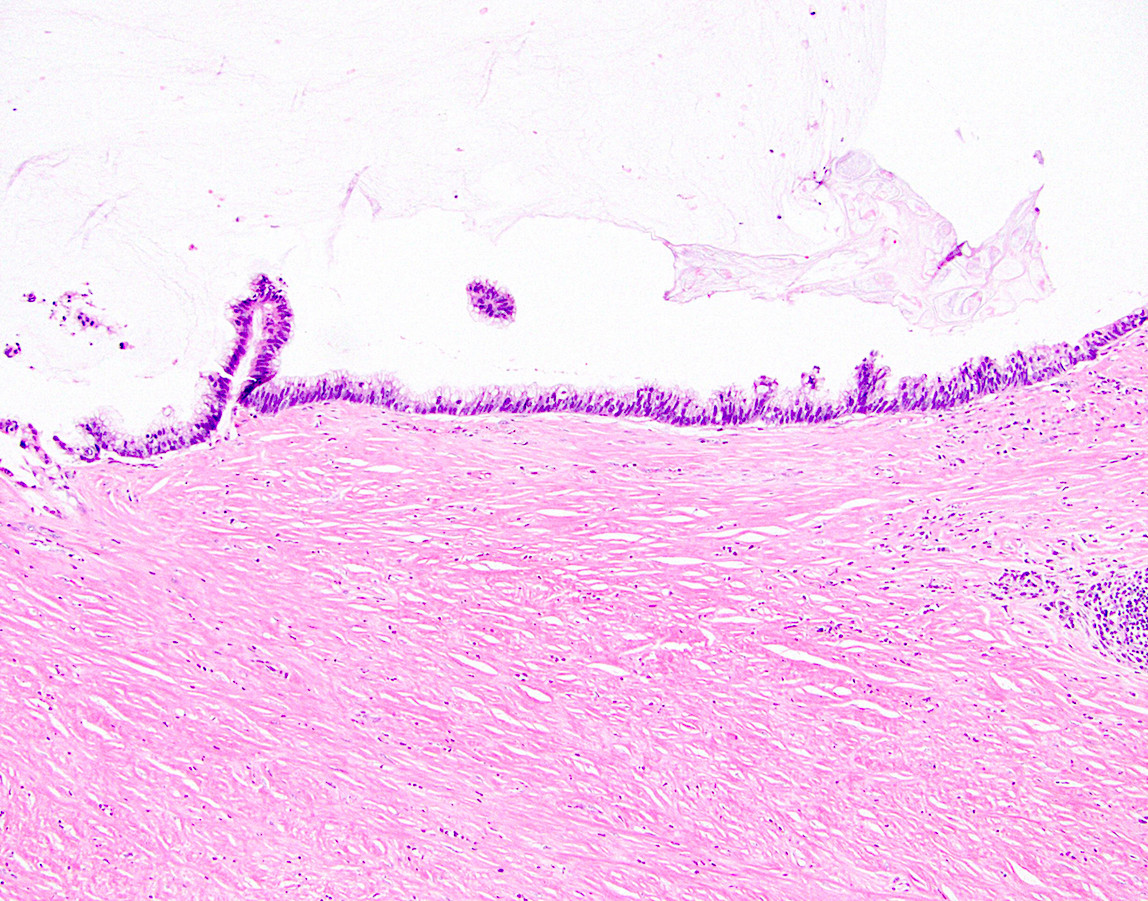

Microscopic (histologic) description

- Villous or occasionally flat proliferation of mucinous epithelial cells originating from appendiceal lumen

- Lesional cells typically demonstrate abundant apical mucin with elongated nuclei and low grade nuclear atypia (LAMN); however, nuclei may appear compressed or rarely high grade (HAMN)

- Often associated with atrophy of underlying lymphoid tissue, crypt loss and effacement of muscularis mucosae

- Broad dissection of mucin, epithelium or both may occur with potential involvement of extra-appendiceal surface, an important finding affecting prognosis

- Extra-appendiceal mucin incites a serosal reaction and may contain neovascularization, assisting in differentiation from benign transfer of mucin during gross examination

Microscopic (histologic) images

Contributed by Raul S. Gonzalez, M.D. and Michael Feely, D.O.